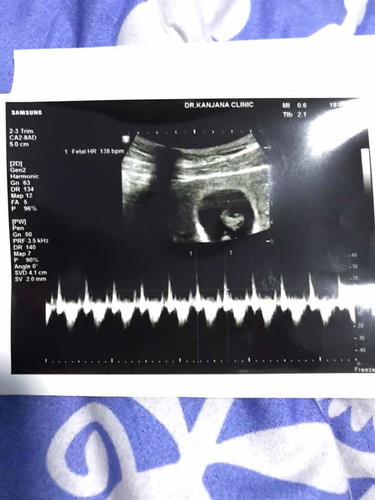

กำลังมีตัวเล็กอายุครรภ์ได้ 8weeks ค่ะ แต่พึ่งรู้ตอน 7weeks 5days เพราะไม่มีอาการแพ้ใดๆ แล้วปกติก็เป็นคนประจำเดือนมาๆหายๆอยู่แล้วเลยไม่ผิดสังเกตุสักอย่างเลยค่ะ จนตอนนี้ก็ไม่มีอาการแพ้ท้องอะไรนอกจากวิงเวียนศรีษะหน้ามืดบางที แบบนี้ถือว่าปกติไหมคะ (คำถามผิดพลาดอย่างไรต้องขอโทษด้วยนะคะมือใหม่จริงๆค่ะ ?)